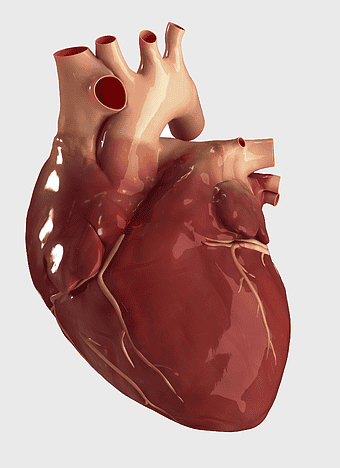

human heart anatomy, cardiovascular system illustration, medical heart diagram, heart organ structure, human body organ visuals, anatomical heart drawing, heart health -

Heart Anatomy Diagram, human heart drawing, realistic heart illustration, cardiovascular system, medical illustration, organ structure, human anatomy study -

human heart anatomy, cardiac muscle illustration, circulatory system model, heart health visual, cardiovascular organ diagram, medical heart image, visceral structure depiction -